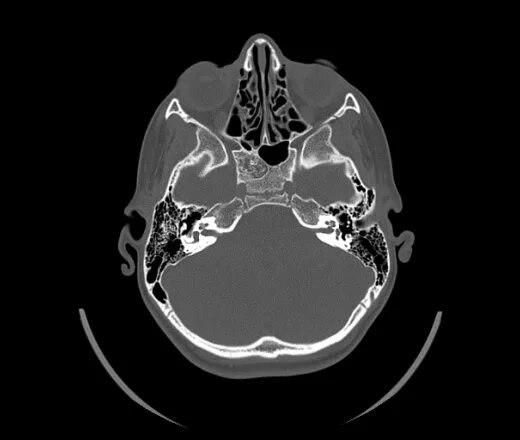

Череп на кт